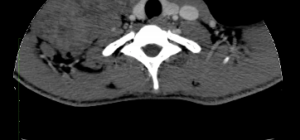

Rhabdomyosarcoma Of The Right Neck (CT) - RadRounds Radiology Network

radrounds.com

radrounds.com

rhabdomyosarcoma radrounds

Cureus | An Unusual Case Of Alveolar Rhabdomyosarcoma Of The Neck In An

www.cureus.com

www.cureus.com

neck ct rhabdomyosarcoma alveolar unusual patient case adult figure scan enlarging mass region showing cureus